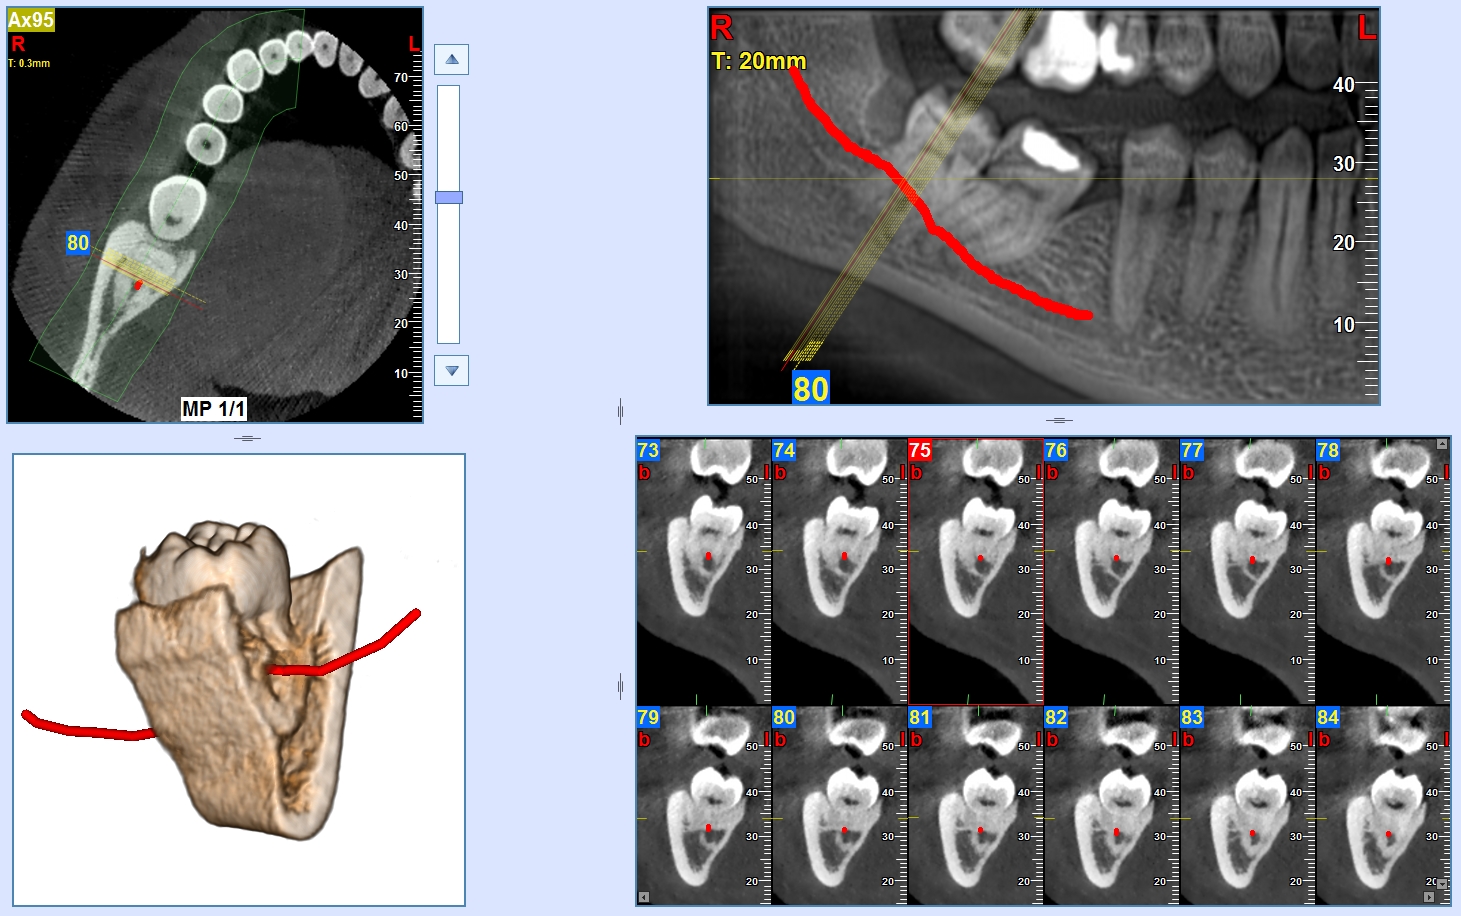

ACCURATA VALUTAZIONE DEL NERVO ALVEOLARE INFERIORE CON LA CONE-BEAM 3D

Una accurata valutazione del percorso del nervo alveolare inferiore è indispensabile per la corretta pianificazione di una avulsione del terzo molare inferiore e per garantire la massima sicurezza al paziente.

L'esame Ortopanoramico, benché minimalmente invasivo per il suo intrinseco basso dosaggio, a causa della sua natura bidimensionale potrebbe fornire informazioni inaffidabili riguardo la relazione tra il canale alveolare inferiore e le radici dei molari. Infatti in casi molto complessi questa informazione potrebbe essere insufficiente e quindi rendersi necessario un esame più approfondito.

Oggi l'Odontoiatra, grazie alla diffusione delle apparecchiature Cone-Beam 3D, ha la possibilità di effettuare valutazioni accurate, anche in studio, su questo tipo di casi con accuratezza ed affidabilità e con una bassa dose radiogena erogata al paziente.

NewTom si distingue per la flessibilità e la usabilità, attraverso la scelta di FOV (*) multipli e risoluzioni variabili e personalizzabili si possono effettuare indagini per una vasta gamma di casi, dalla classica Chirurgia alla Endodonzia e Parodontologia. Il sistema SafeBeam™ permette alla macchina di scegliere in modo automatico i parametri radiologici corretti, utilizzando così il minore dosaggio per il paziente. Gli strumenti intuitivi forniti con il software NNT permettono di misurare angoli e distanze, pianificare un trattamento implantare, evidenziare il canale mandibolare. Il potente motore 3D permette di creare delle rappresentazioni tridimensionali del volume acquisito della massima efficacia e comunicatività.